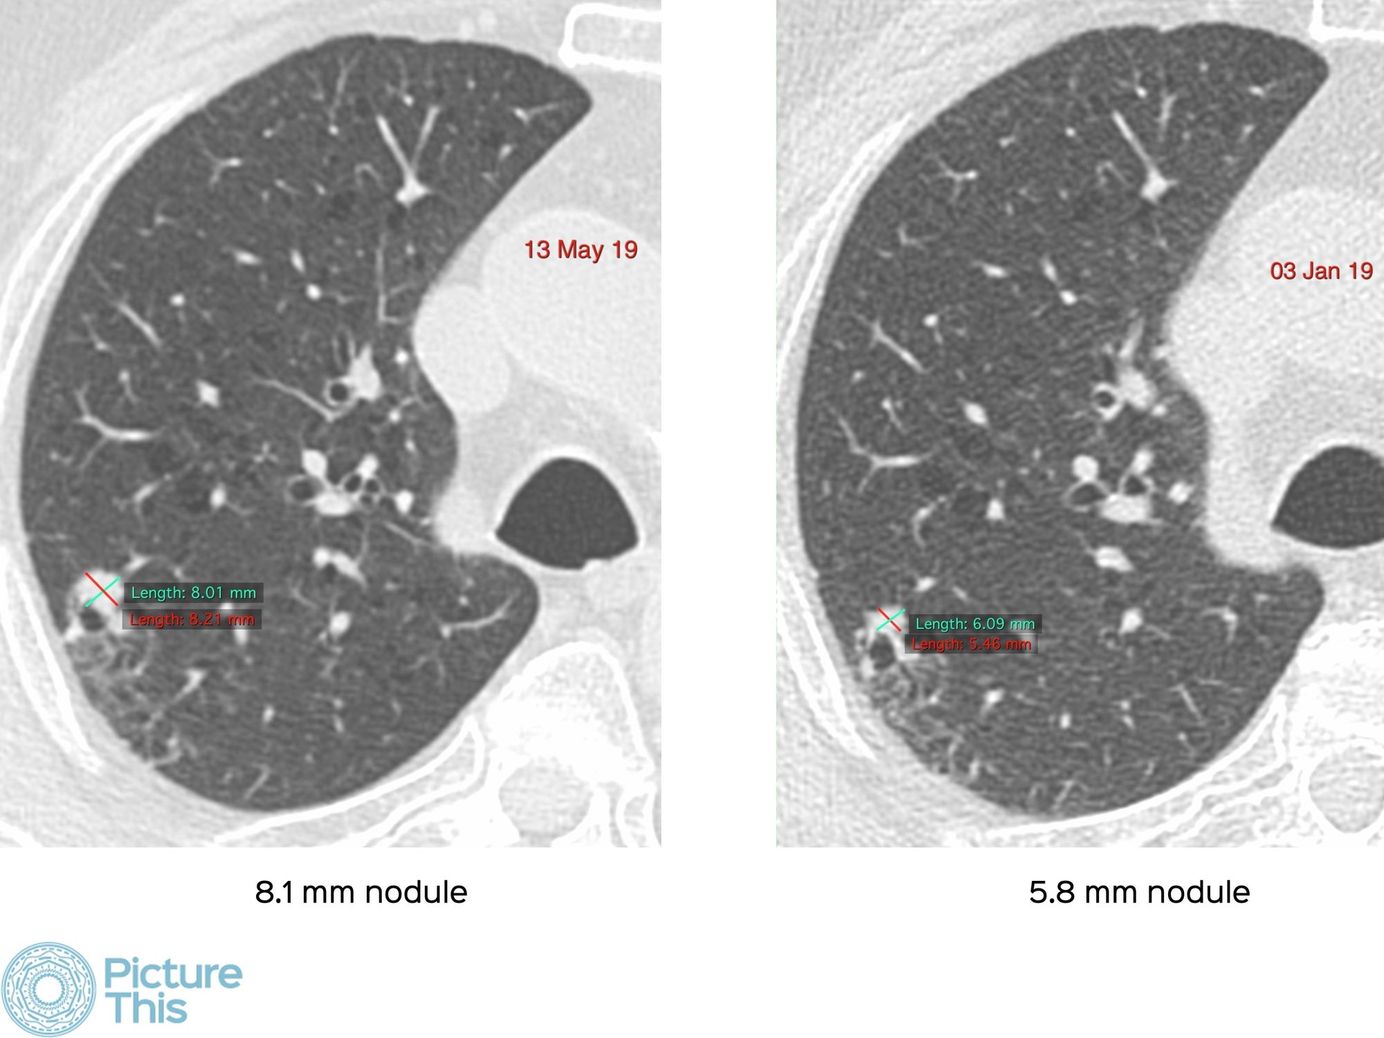

Lecture 1: High Risk CT Imaging Features in Lung Cancer Screening Members Public

Describing the various signs that allows us to pick up Lung-RADS 4A and 4B lesions